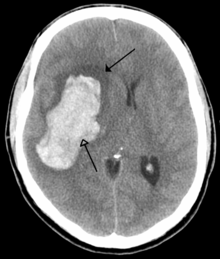

CT scan of an intraparenchymal bleed (bottom arrow) with surrounding edema (top arrow)

There are two main types of hemorrhagic stroke:[21][22]